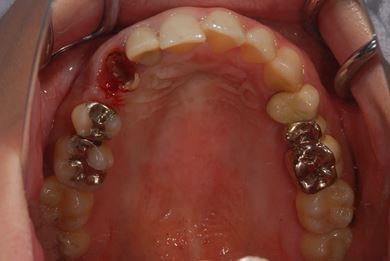

インプラントの症例写真 IMPLANT

抜歯即日スピードインプラント治療

| 性別/年齢 | 女性 / 29歳 | ||||||||||||||||||||||||||||||||

| 主訴 | 以前治療中のままだった部位の歯の根に膿が溜まって、痛みと腫れが出た。応急処置で切開して膿は取ってもらったが、根の治療がまだなので、お願いしたい。 | ||||||||||||||||||||||||||||||||

| 治療方針 | 抜歯と同時にインプラント埋入を行い、治療期間を短縮する。 | ||||||||||||||||||||||||||||||||

| 治療内容 | インプラント2本(抜歯即日スピードインプラント)、ハイブリッドセラミッククラウン3本 | ||||||||||||||||||||||||||||||||